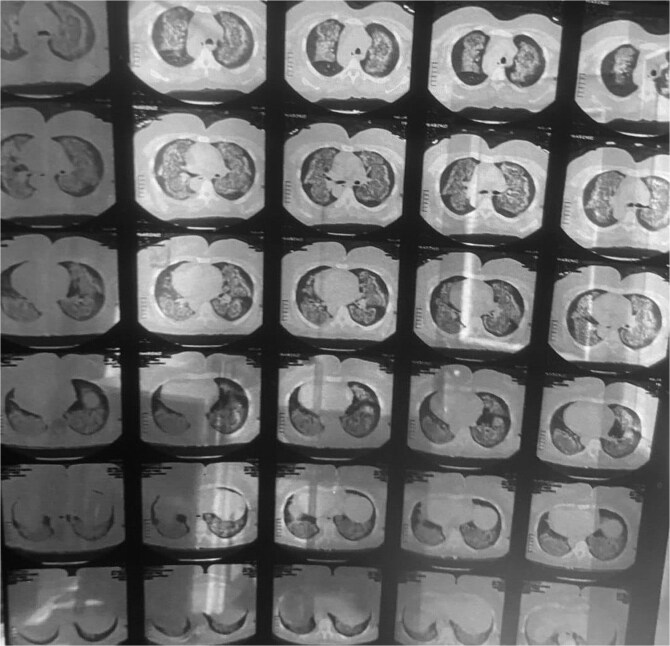

系统性红斑狼疮(SLE)是一种自身免疫性全身性疾病,由于其广泛的临床表现影响多个器官,因此对诊断提出了挑战。特别罕见的是弥漫性肺泡出血(DAH),这是一种由毛细血管-肺泡屏障破坏引起的严重并发症,可迅速发展为危及生命的疾病。我们报告一例57岁的女性谁提出到急诊科经历呼吸困难和咯血。她的初步评估显示贫血和血小板减少,高分辨率计算机断层扫描显示弥漫性双侧浸润,表明DAH。这些发现导致了先前未被识别的SLE的诊断。该病例强调了在鉴别诊断DAH时考虑SLE的重要性,强调了及时诊断和积极治疗的必要性,以改善患者的预后。

Systemic lupus erythematosus (SLE) is an autoimmune systemic disease that presents a diagnostic challenge due to a wide range of clinical manifestations affecting multiple organs. Particularly rare is its presentation with diffuse alveolar hemorrhage (DAH), a severe complication that arises from the disruption of the capillary-alveolar barrier and can rapidly progress to a life-threatening condition. We report a case of a 57-year-old female who presented to the emergency department experiencing dyspnea and hemoptysis. Her initial evaluations revealed anemia and thrombocytopenia, with high-resolution computed tomography scans showing diffuse bilateral infiltrates indicative of DAH. The findings led to the diagnosis of previously unrecognized SLE. This case underscores the importance of considering SLE in the differential diagnosis of DAH, emphasizing the necessity for prompt diagnostic workup and aggressive treatment in such critical presentations to improve patient outcomes.